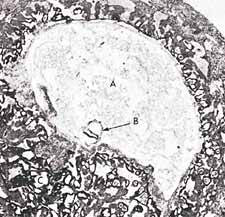

Figure 3: In this photomicrograph, we can see the suspension of an embryo (marked B) during the alaqah stage (about 15 days old) in the womb of the mother.  The actual size of the embryo is about 0.6 mm. (The Developing Human, Moore, 3rd ed., p. 66, from Histology, Leeson and Leeson.)

Figure 3